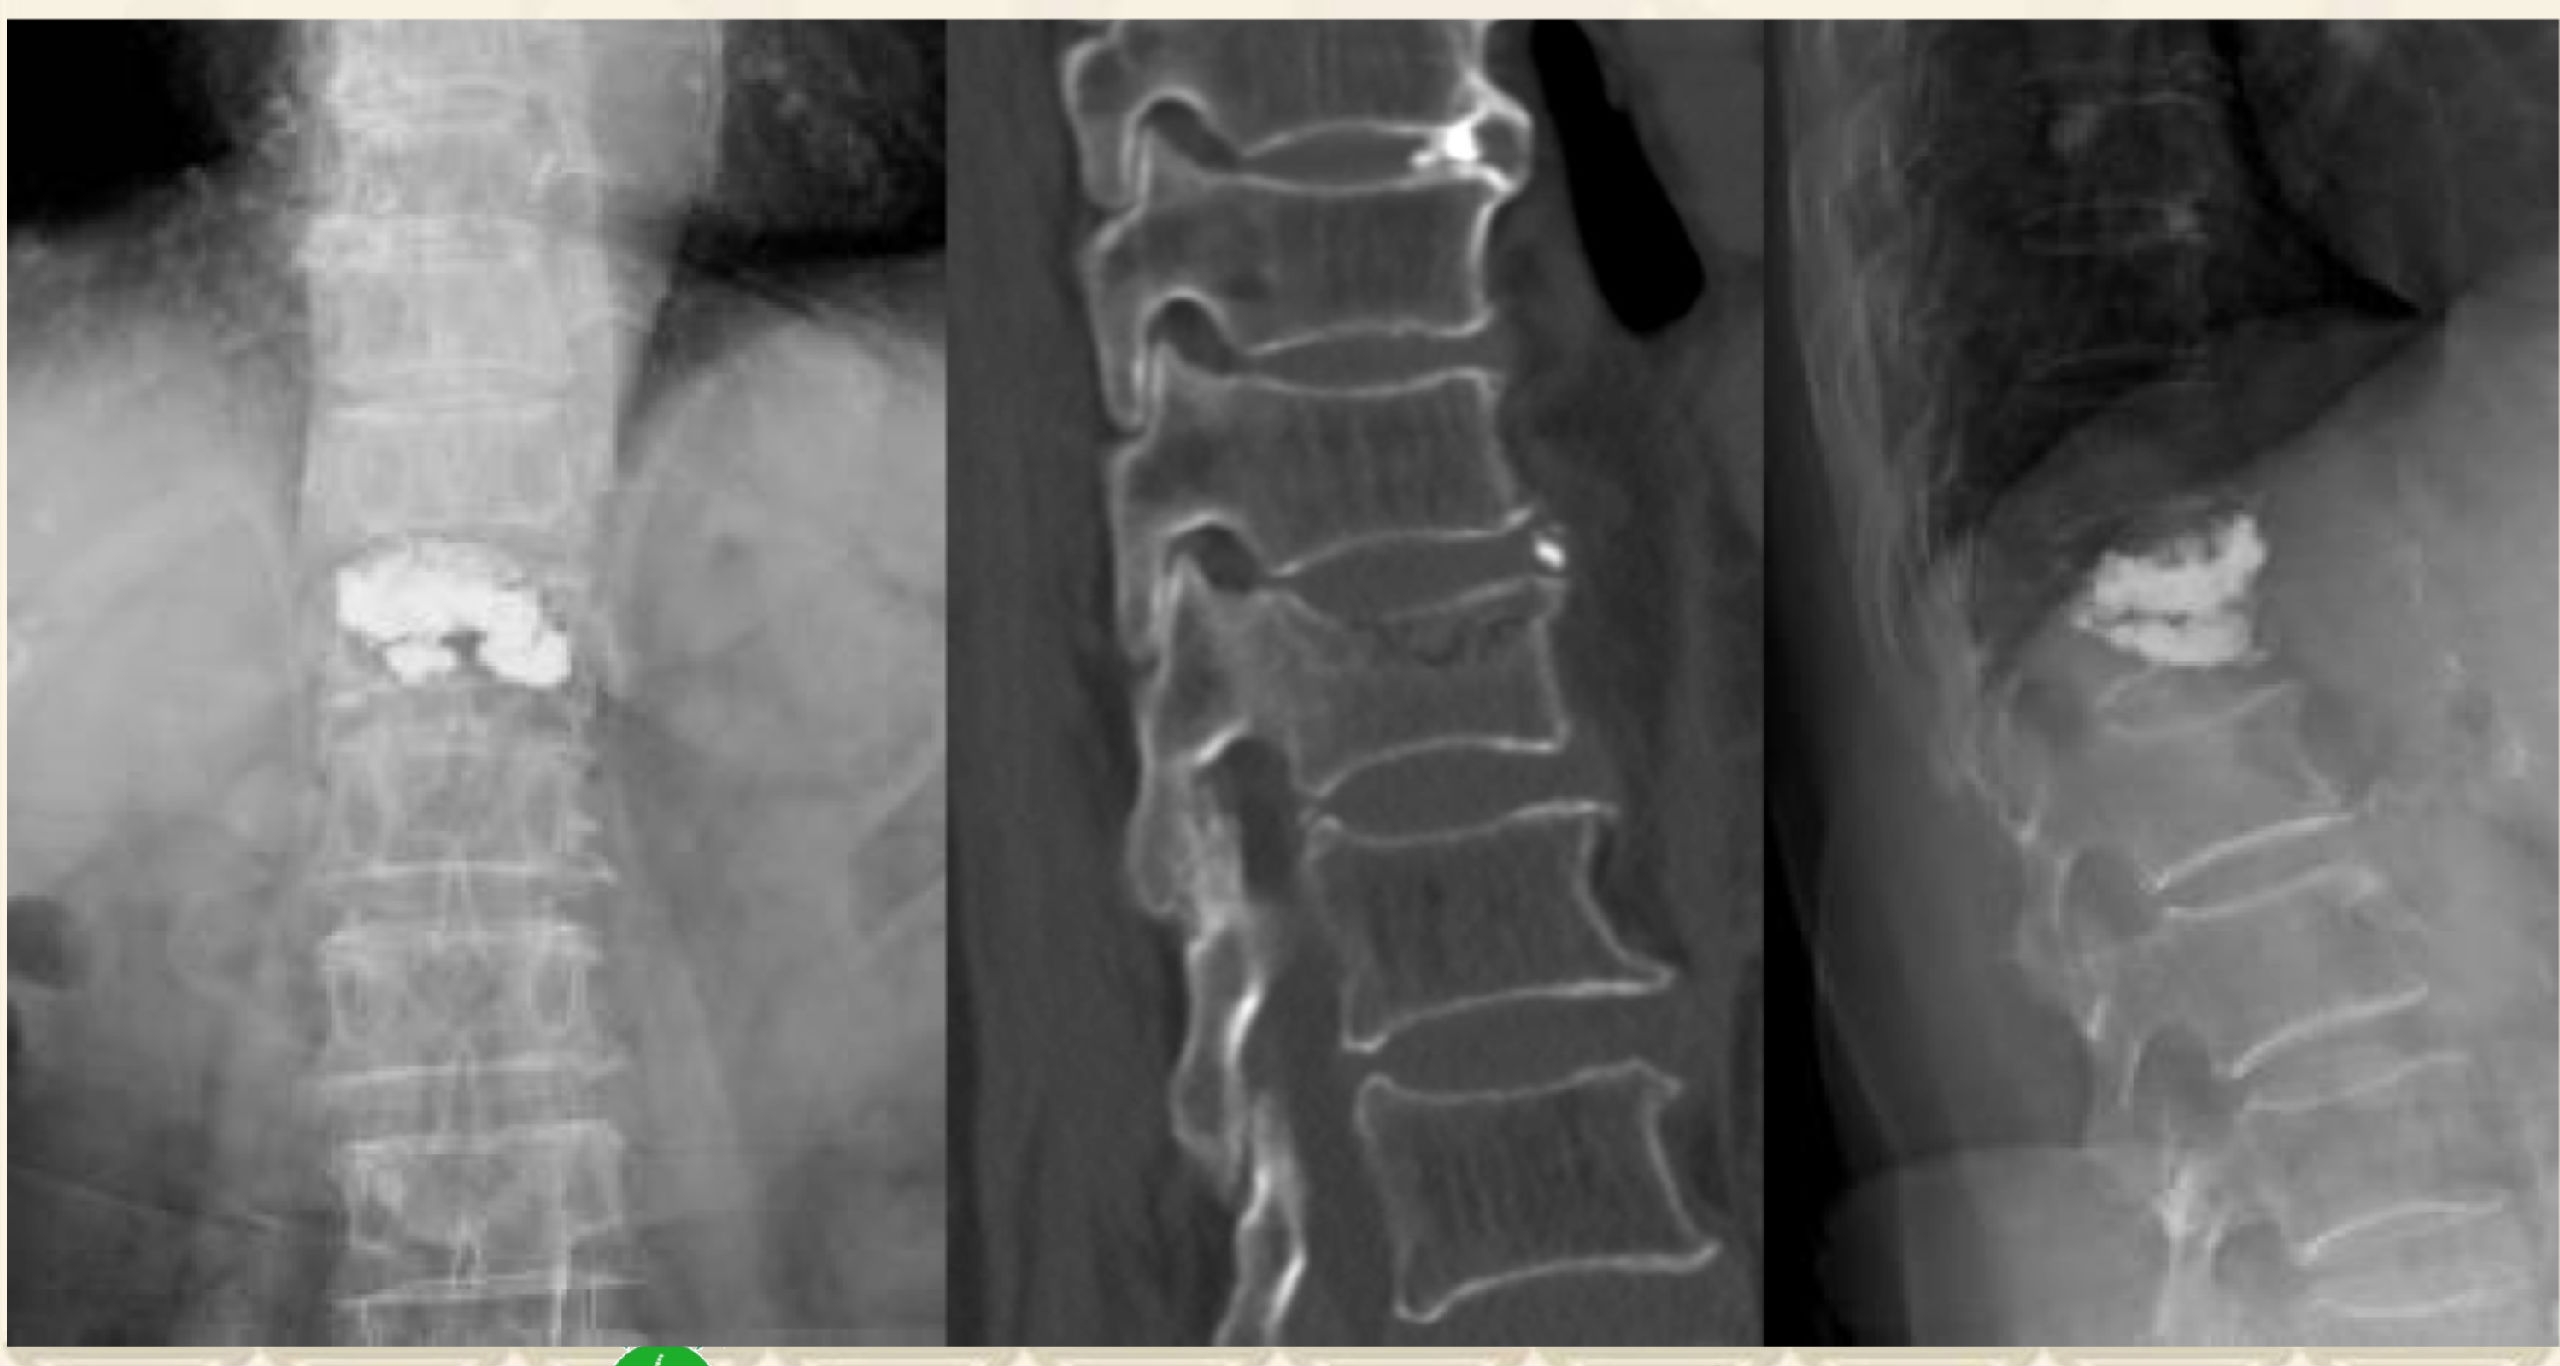

术前X线

术前MRI

术前CT

术后X线

术后CT